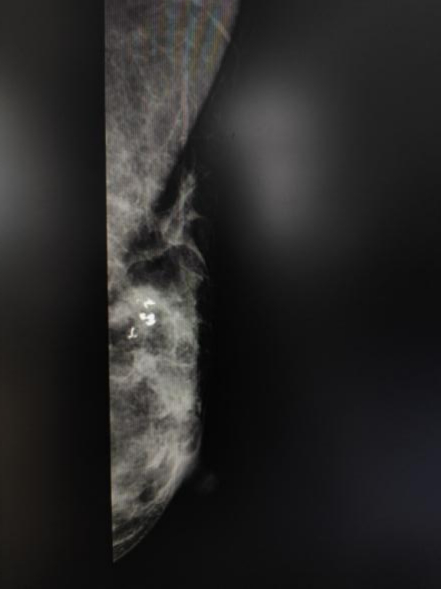

乳腺钼靶需要做吗

B超和钼靶是不一样的两种检查,B超的优点能敏感地发现结节或肿块,鉴别囊性或者实体肿块的准确率达到100%;而钼靶则是能发现B超发现不了的微小钙化灶,因为有些肿瘤首发的不是实体肿块,而是非常细小、广泛的钙化灶。如果钙化灶大小不一,形态各异,簇状聚集或是沿乳腺导管线性排列等,这些征象提示恶性钙化。已有研究表明,两种检查联合起来,可以提高乳腺癌的检出率。

钼靶图像(白点为钙化灶)

除了诊断的作用外,B超和钼靶还可以协助定位手术目标病灶。我们为了精准地切除病灶,常规使用的术前定位都是B超定位;对于只有钼靶发现的病灶,可以利用钼靶定位,置入金属导丝,有助于术中精准切除病灶。

术前钼靶导丝定位

一般建议B超3-6月复查一次,对于小于40岁女性,乳房致密,不建议做钼靶X线筛查,对于乳腺癌高危人群可以在40岁以下做筛查,必要时可以结合B超检查。40岁以上的女性1-2年做一次钼靶X线检查。